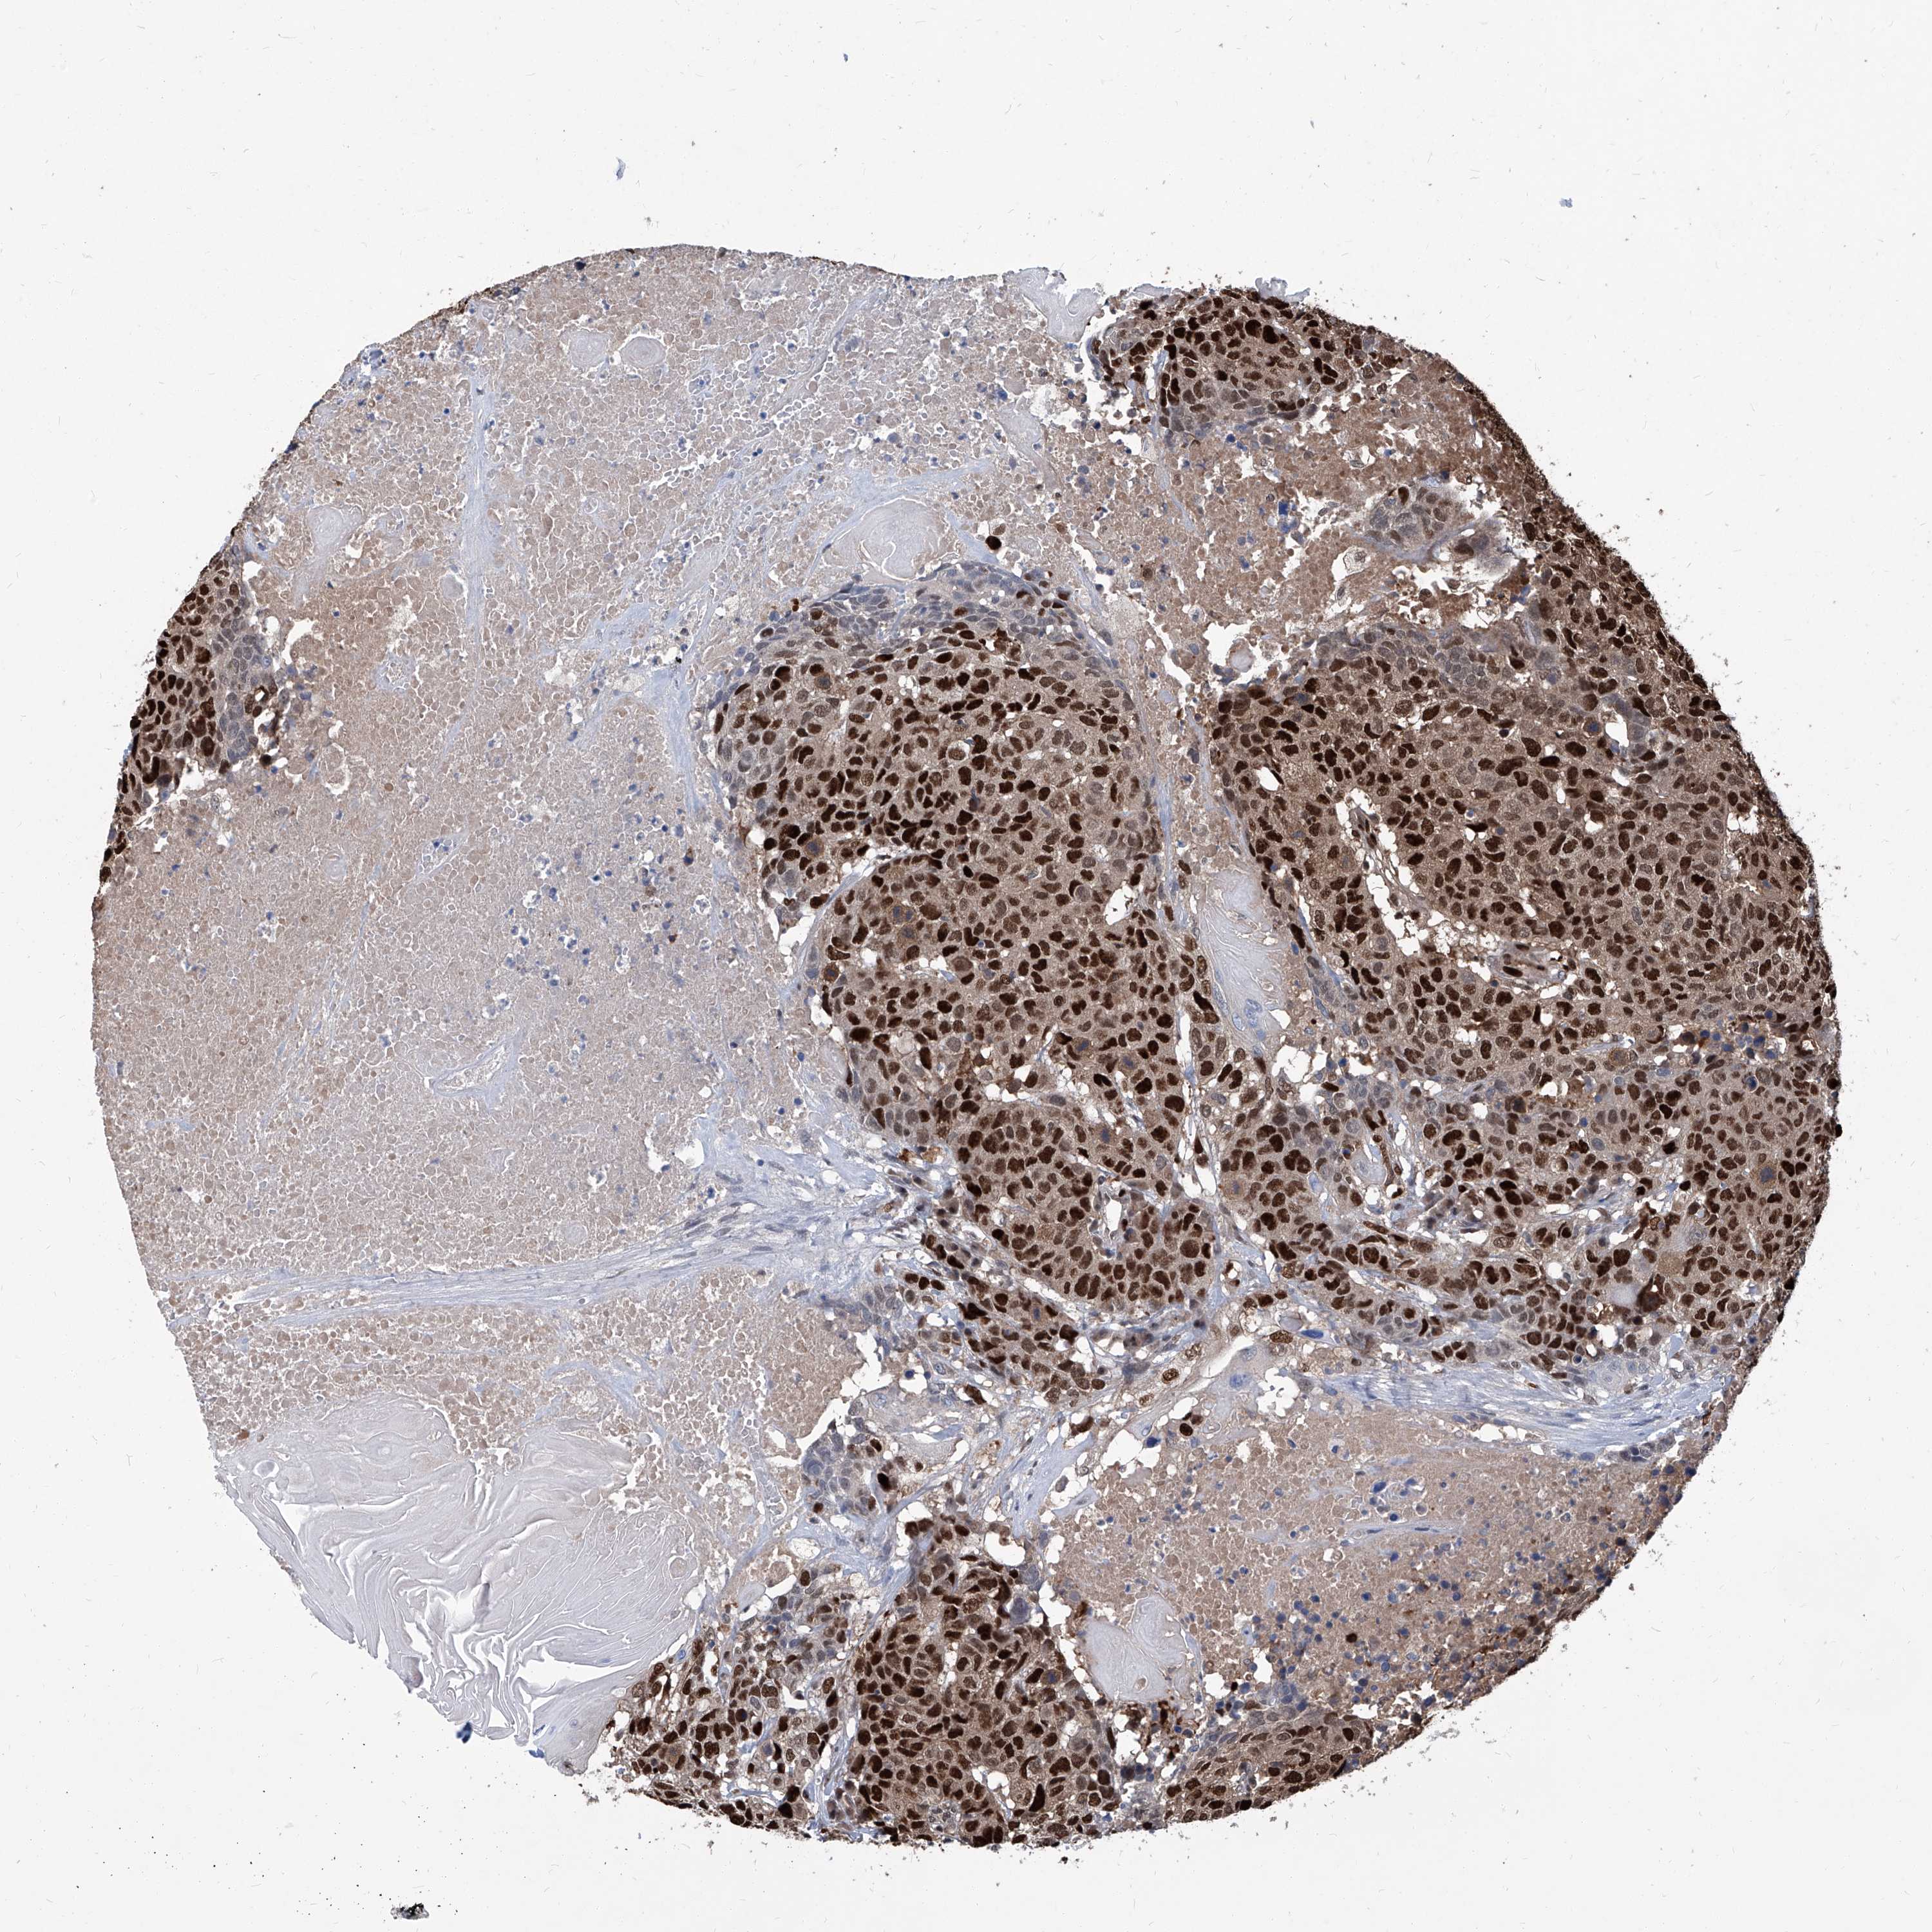

HEAD AND NECK CANCER - Protein expressioni

A mouse-over function shows sample information and annotation data. Click on an image to view it in a full screen mode. Samples can be filtered based on level of antibody staining by selecting one or several of the following categories: high, medium, low and not detected. The assay and annotation is described here.

Note that samples used for immunohistochemistry by the Human Protein Atlas do not correspond to samples in the TCGA dataset.

Antibody stainingi

Antibody staining in the annotated cell types in the current human tissue is reported as not detected, low, medium, or high, based on conventional immunohistochemistry profiling in selected tissues. This score is based on the combination of the staining intensity and fraction of stained cells.

Each image is clickable and will lead to virtual microscopy that enables deeper exploration of all samples and also displays staining intensity scores, fraction scores and subcellular localization as well as patient and tissue information for each sample.

Squamous cell carcinoma, NOS